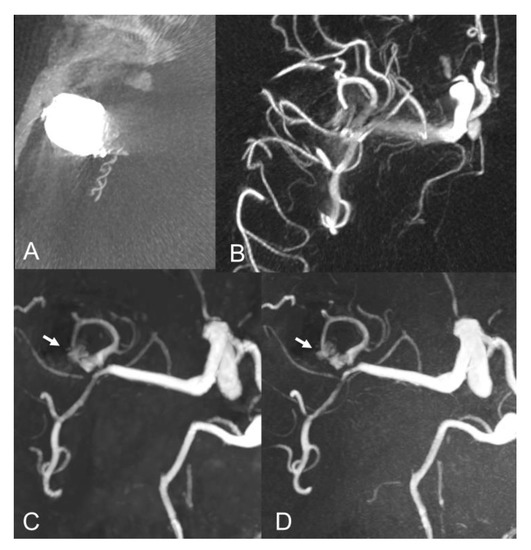

Figure 3.

Baseline axial CT image (A) and vaso-CT (B) after stent-assisted coiling of a middle cerebral artery aneurysm. Follow-up axial MIP images of CS TOF (C) and PI TOF (D) showing residual flow (arrows) between the coils (class IIIb).

Our findings are in agreement with previous studies which showed comparable results between CS TOF and PI TOF MRA in the detection of a variety of cerebrovascular pathologies, including aneurysms, stenosis and arteriovenous shunts [21,22,23,24,25]. In particular, no significant differences were found between CS TOF and PI TOF MRA in the depiction of intact aneurysms, as well as in the measurement of neck, height and width of aneurysms [22]. In our study, only one case received a different occlusion classification in CS and PI TOF images, by the neurointerventionalist reader, who correctly appreciated a small neck remnant in CS TOF images, which was not apparent in the PI sequence (Figure 2). Therefore, while magnetic susceptibility artifacts due to the presence of the coil cast seem to have a comparable effect on both sequences in the majority of cases, we observed a sharper interface between blood flow and surrounding coils in some CS TOF images compared to PI TOF counterparts (Figure 1, Figure 2 and Figure 3).